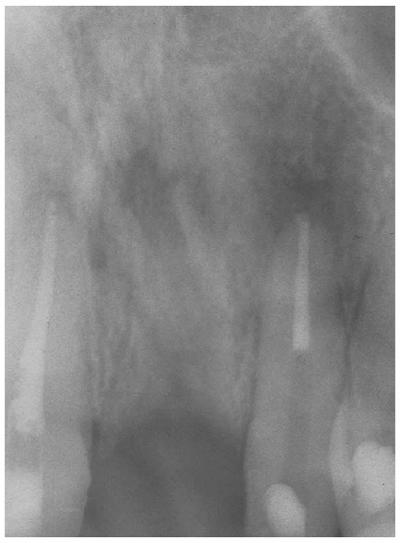

restoration of endodontically treated teeth (Figur 323s1823d es 18-20A 18-20B, and 18-20C). If an adequate ferrule is

obtained, the type, material, and design of the post and core become much less

important. Conversely, if a ferrule is not obtained, then the tooth is at risk

of fracturing no matter what type of post and core is used. This is especially

true for teeth that are expected to carry a heavy load such as a removable

partial denture or fixed partial denture abutment or in patients who exhibit

excessive wear or bruxism.

Figur 323s1823d e 18-19: Ferrule design resists wedging force of post.

Figur 323s1823d e 18-20A: Proper ferrule design on preparation for porcelain-fused-to-metal crown.

Figur 323s1823d e 18-20B: Radiograph showing cast post and core after cementation. Note that the post is more than one-third of the diameter of the root at the cement-enamel junction and is tapered. Tooth preparation did not exhibit ferrule design.

Figur 323s1823d e 18-20C: Same clinical case as in Figur 323s1823d e 18-20B after 8 years. Note the oblique root fracture. Such a fracture could be prevented by a more conservative post in combination with proper ferrule design in the crown preparation.